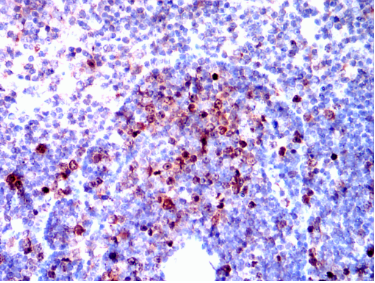

AURKB Mouse Monoclonal antibody[13E8D]

AURKB (aurora kinase B, AIK2 or aurora-B), with 344-amino acid protein(about 39kDa),localizes to microtubules near kinetochores, specifically to the specialized microtubules called K-fibers. AURKB is a mitotic protein kinase, which phosphorylates histone H3 and regulates Chromosomal segregation during mitosis and meiosis.It may regulates several stages of mitosis such as centrosome separation, chromosome segregation and cytokinesis.Component of the chromosomal passenger complex (CPC), a complex that acts as a key regulator of mitosis. The CPC complex has essential functions at the centromere in ensuring correct chromosome alignment and segregation and is required for chromatin-induced microtubule stabilization and spindle assembly. ARK-2 transcripts arepresent at high levels in human thymus and fetal liver.ARK-2 protein levels are maximal during both S and G2/M phases

IHC    1/200 - 1/1000